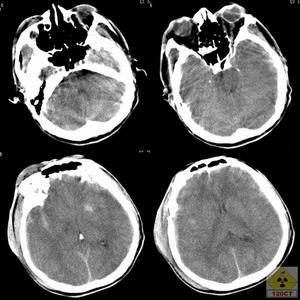

3.顱腦CT掃描CT掃描對顱骨碎片、彈片、創道、顱內積氣、顱內血腫、瀰漫性腦水腫和腦室擴大等情況的診斷,既正確又迅速,對內科療效的監護也有特殊價值。

(2)腦膨出

③X線檢查:顱內有無碎骨片和金屬異物,懷疑腦膿腫或血腫時行CT掃描。

④治療:術後腦水腫和局部感染所致者,採用脫水療法和抗感染治療,腦膨出部分以棉圈保護,膨出的基底部每日清潔,防止膿性分泌物瀦留,一般經非手術療法多能治癒。顱內血腫或腦膿腫所致者,應行開顱血腫清除或腦膿腫切除。